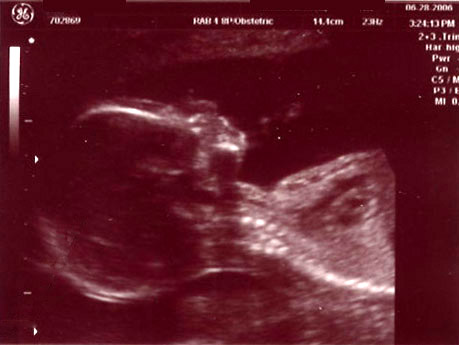

| June 28, 2006 - Twenty Week Ultrasound: IT'S A BOY!!! |

Today was probably the

longest day of my life having to wait for our 3:00pm appointment. I

went to work today, but didn't get much done since I was so excited to

finally find out what we were having. We got to the doctor's and they

took us right away. Within 44 seconds of the technician turning on the

ultrasound machine, she showed us the picture of the legs spread wide open

and it was obvious that we were having a boy!! He was so active

throughout the entire ultrasound, kicking and turning all over the place.

He is absolutely beautiful!!! I am in love with him already. He

weighed 13.5 ounces and he is perfect and healthy!! We are so excited

to start planning the nursery for our little man. Here are the

ultrasound pics from today. Enjoy!! ~Jen

Head shot of the little man |